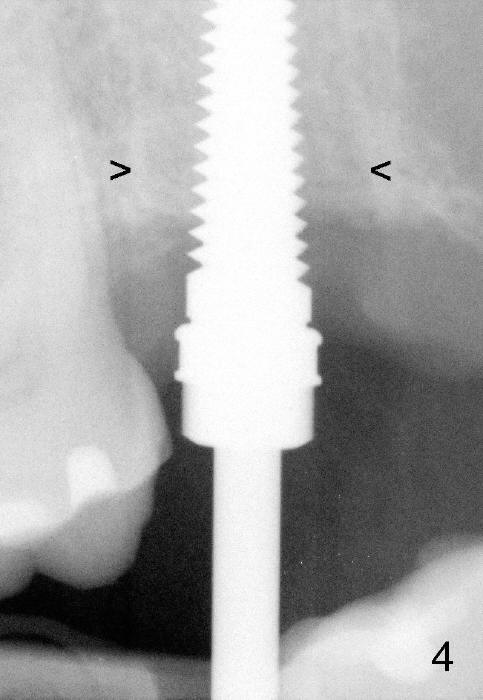

A 57-year-old lady presents for abscess buccal to the tooth #15 (Fig.1 A). Mesial and distal to the occlusal composite (Fig.2 C) is a crack line. In addition to long furcated roots, the upper border of the bone is not shown in this preop PA (arrow). Fig.3 is taken to show a thin septum surrounded by the mesiobuccal (MB), distobuccal (DB) and palatal (P) sockets (Fig.3). Osteotomy is initiated in the septum by 1.2 and 1.5 mm pilot drills, followed by 2,3,4 mm rounded tapered osteotomy at the depth of 17 mm. Nose blowing test is carried out after each step with negative result. Stability is achieved when a 4.5 mm tap is inserted at 17 mm, but the upper end of the tap is not visible (Fig.4,5). When a 5 mm tap is placed, stability is decreased, probably because the coronal end of the septum starts to break down (due to expansion). To re-gain stability, the 5 mm tap needs to go deeper. A 6 mm tap also achieves satisfactory stability at 20 mm. When the tap is removed, there is no air leakage. A 6x20 mm implant is placed with insertion torque > 60 Ncm; the upper end of the implant is still out of view in PA (Fig.6). Another problem is that the implant needs to go deeper to obtain sufficient occlusal clearance. The lower first molars and the 2nd premolars are missing. A panoramic X-ray has to be taken to show the apical end of the implant: ~ 3 mm into the sinus (Fig.7 ^). The maxillary tuberosity appears to grow downward (arrow). In other word, the tooth #15 appears to have been intruded due to overloading.